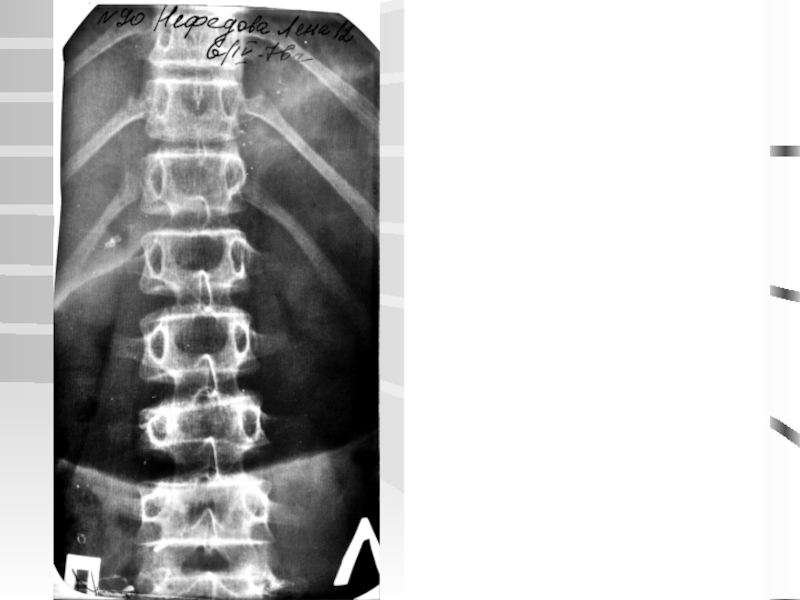

Слайд 38Диагностика

Рентгенологические

Клинические

Методы

ДиагностикаРентгенологическиеКлиническиеМетод КОМОТМетоды

Слайд 39по Липману-Коббу, 1935

по Фергюссону

Fergusson

Cobb

Угол сколиотической дуги

Угол сколиоза

по Липману-Коббу, 1935по ФергюссонуFergusson Cobb Угол сколиотической дугиУгол сколиоза